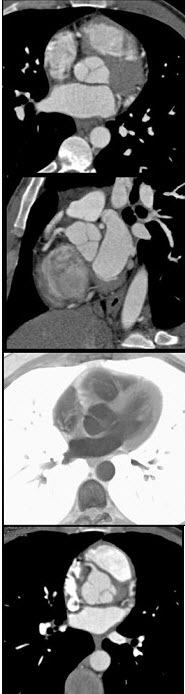

图中冠状动脉造影结果为( )

A:左主干近端95%狭窄

B:右冠远端95%狭窄

C:左冠回旋支95%狭窄

D:右冠中段95%狭窄

E:左冠前降支近端95%狭窄